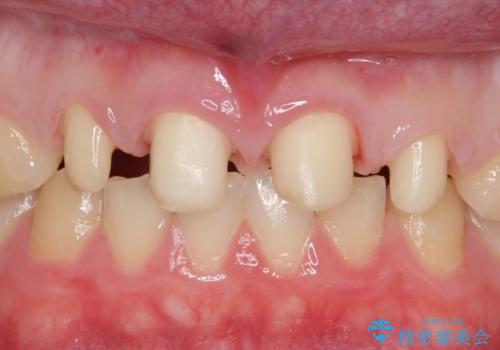

- 前歯の隙間を埋めたいとのことで来院された患者様です。

矯正治療とかぶせ物での治療どちらともご提案したところ、かぶせ物での治療をご希望されたためクラウンでの審美性回復を試みることとなりました。

今回のように、元の歯が小さすぎる場合は矯正治療での審美性回復が難しいことがあります。